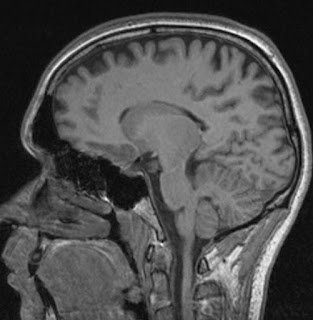

Several scans have been conducted to check her condition.